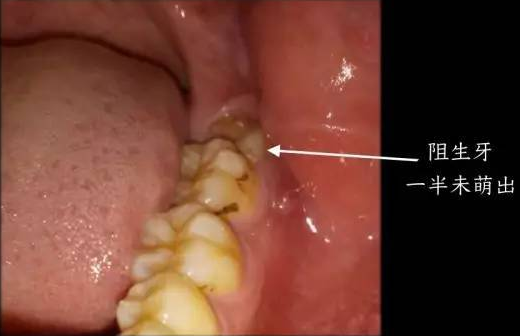

两边智齿阻生齿的图片

这种智齿萌出一部分,而且位置不正,容易反复发作,需要重点观察

智齿在颌骨内由于位置不当,不能萌出到正常咬合位置,被称为阻生智齿.